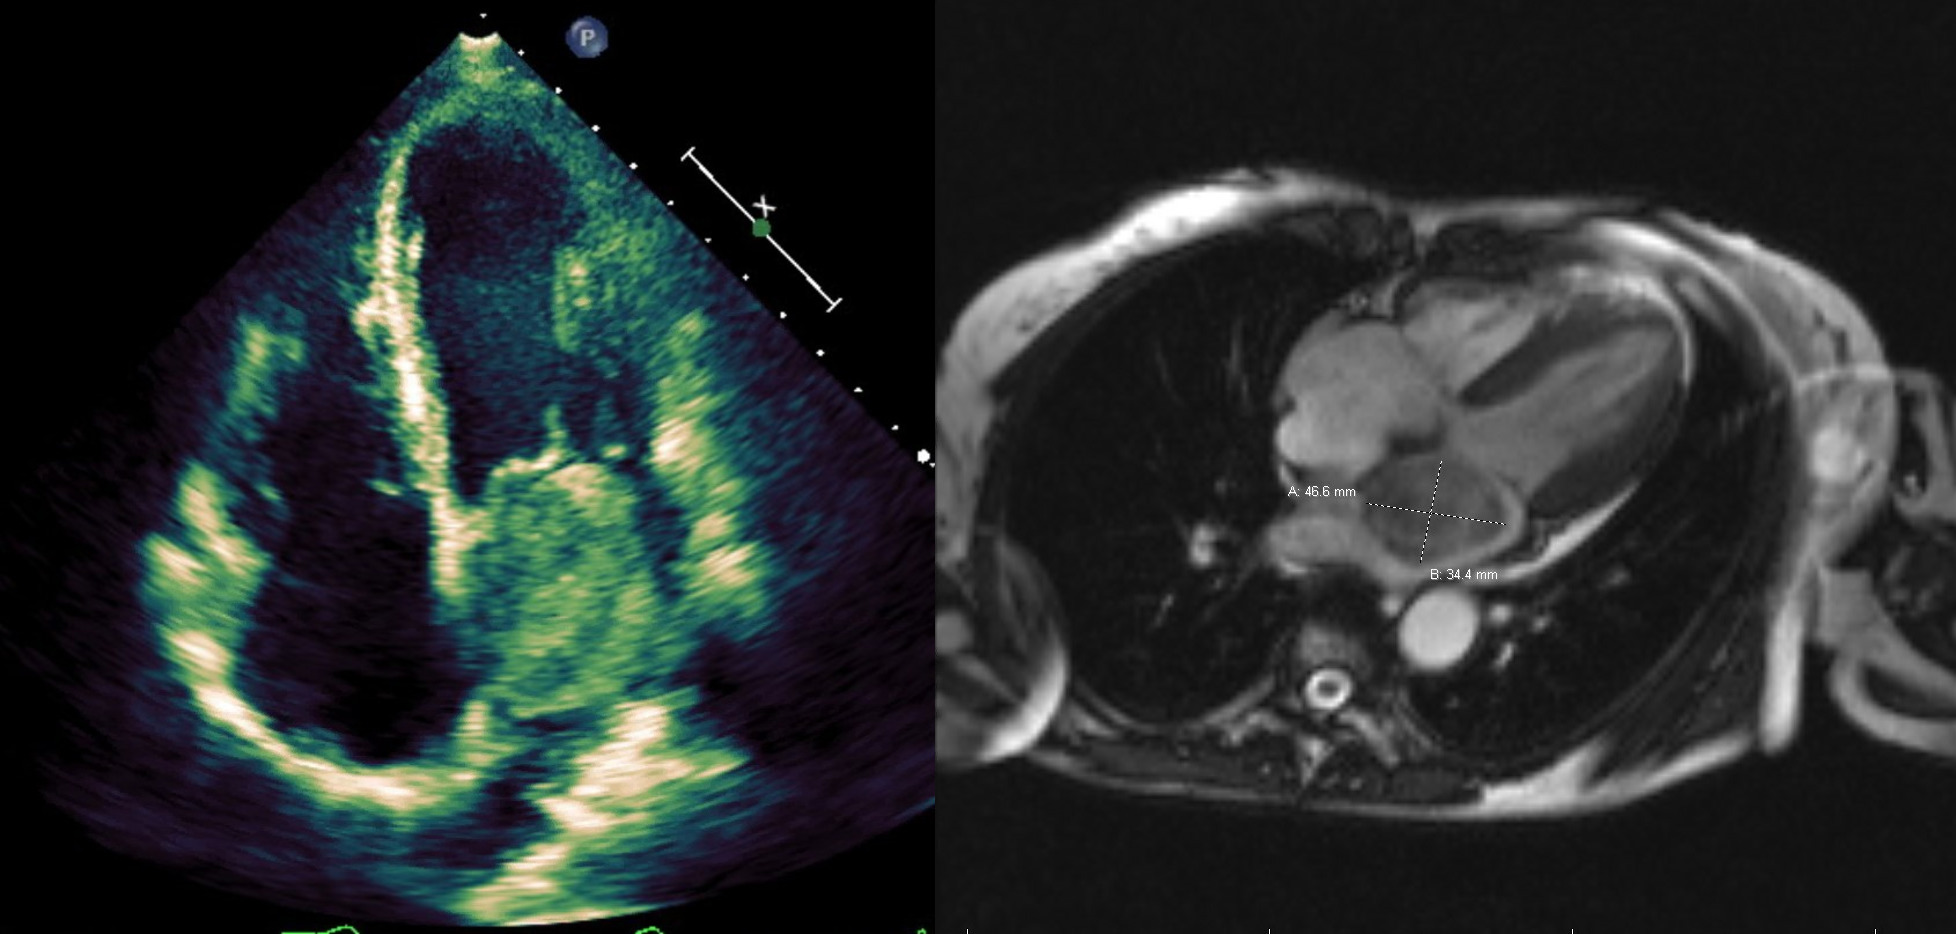

The patient noted no improvement in symptoms despite three days of escalating IV diuresis. Transthoracic echocardiography (TTE) revealed a 40% ejection fraction (EF), decreased left ventricular systolic function, and a large echogenic mass in the left atrium (LA), which was confirmed on transesophageal echocardiography (TEE). The mass was noted to be a heterogenic structure measuring 4.8×4.0 cm in the LA with a stalk (0.83 cm) extending from the interatrial septum. During diastole, the mass was noted to prolapse into the mitral valve without complete obstruction of flow. Cardiac MRI was significant for a 3.4×4.7cm pedunculated mass in the LA attached to the interatrial septum, consistent with a myxoma. After extensive discussion regarding the risks and benefits of surgical intervention were held with the patient, family, and members of the primary, cardiology, and cardiothoracic surgery services, myxoma excision was pursued. Pre-operative left heart catherization showed non-obstructive coronary artery disease of the right coronary artery. The patient then underwent successful atrial myxoma (39.3 grams) removal with repair of subsequent atrial septal defect with bovine pericardial patch. She tolerated the procedure well and was transferred to the intensive care unit for monitoring, where she was extubated within 24 hours. Pathology confirmed benign growth composed of primitive connective tissue cells in a myxomatous stromal background, consistent with a myxoma. The patient had steady clinical improvement and she was discharged to home 6 days after her operation. On follow-up, the patient noted complete resolution of symptoms. Repeat TTE at 3 and 12 months after discharge noted normal EF with no myxoma reoccurrence.